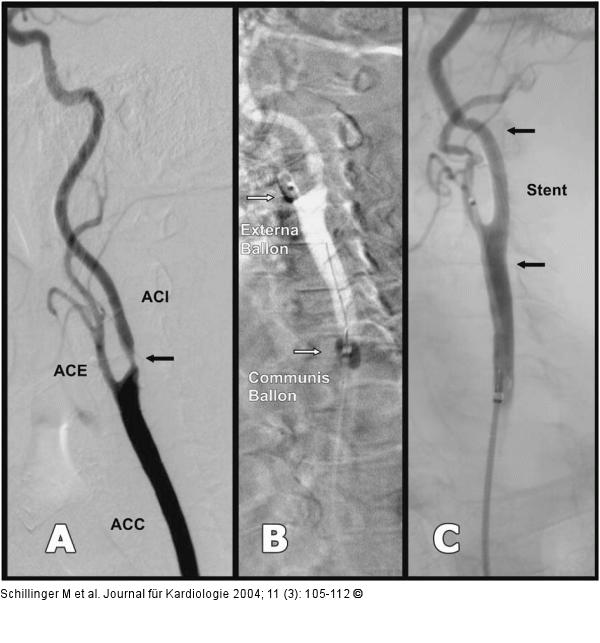

Abbildung 3A-C: Karotisstenose - Stent Karotisstentangioplastie einer hochgradigen Arteria carotis interna-Stenose unter Verwendung eines proximalen Ballonokklusionssystems (MoMa, Fa. Invatec.). A) ACI-Stenose, B) Ballonokklusion in der ACE und ACC, C) Abschlußbild nach Stent (ACC = Arteria carotis communis; ACI = A. c. interna; ACE = A. c. externa) |

Abbildung 3A-C: Karotisstenose - Stent

Karotisstentangioplastie einer hochgradigen Arteria carotis interna-Stenose unter Verwendung eines proximalen Ballonokklusionssystems (MoMa, Fa. Invatec.). A) ACI-Stenose, B) Ballonokklusion in der ACE und ACC, C) Abschlußbild nach Stent (ACC = Arteria carotis communis; ACI = A. c. interna; ACE = A. c. externa) |